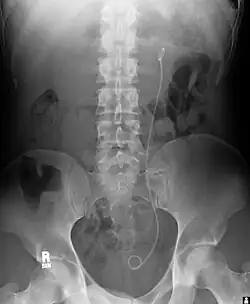

Ureteric stent

Ureteral stents are used to ensure the patency of a ureter, which may be compromised, for example, by a kidney stone. This method is sometimes used as a temporary measure to prevent damage to a kidney caused by a kidney stone until a procedure to remove the stone can be performed.

An ureteral stent it is typically inserted using a cystoscope, and one or both ends of the stent may be coiled to prevent movement. Ureteral stents are used for various purposes, such as temporary measures to prevent damage to a blocked kidney until a stone removal procedure can be performed, providing drainage for compressed ureters caused by tumors, and preventing spasms and collapse of the ureter after trauma during procedures like stone removal. The thread attached to some stents may cause irritation but allows for easy removal by pulling gently.

Stents without threads require cystoscopy for removal. Recent developments have introduced magnetic retrieval systems that eliminate the need for invasive procedures like cystoscopy when removing the stent. The use of magnets enables simple extraction without anesthesia and can be done by primary care physicians or nurses rather than urologists. This method has shown high success rates across different patient groups including adults, children, and kidney transplant patients while reducing costs associated with operating room procedures.